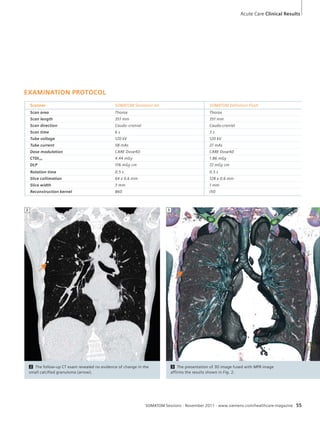

1A Standard WFBP. Standard weighted

filtered back projection reconstruction

using an H40 kernel.

1B This image visualizes image quality based

on SAFIRE achieved with only 14.74 mGy.

Significantly decreased image noise without

loss of resolution or gray-white matter differenti-ation

can be seen.

1A 1B

levels of dose and the image quality.